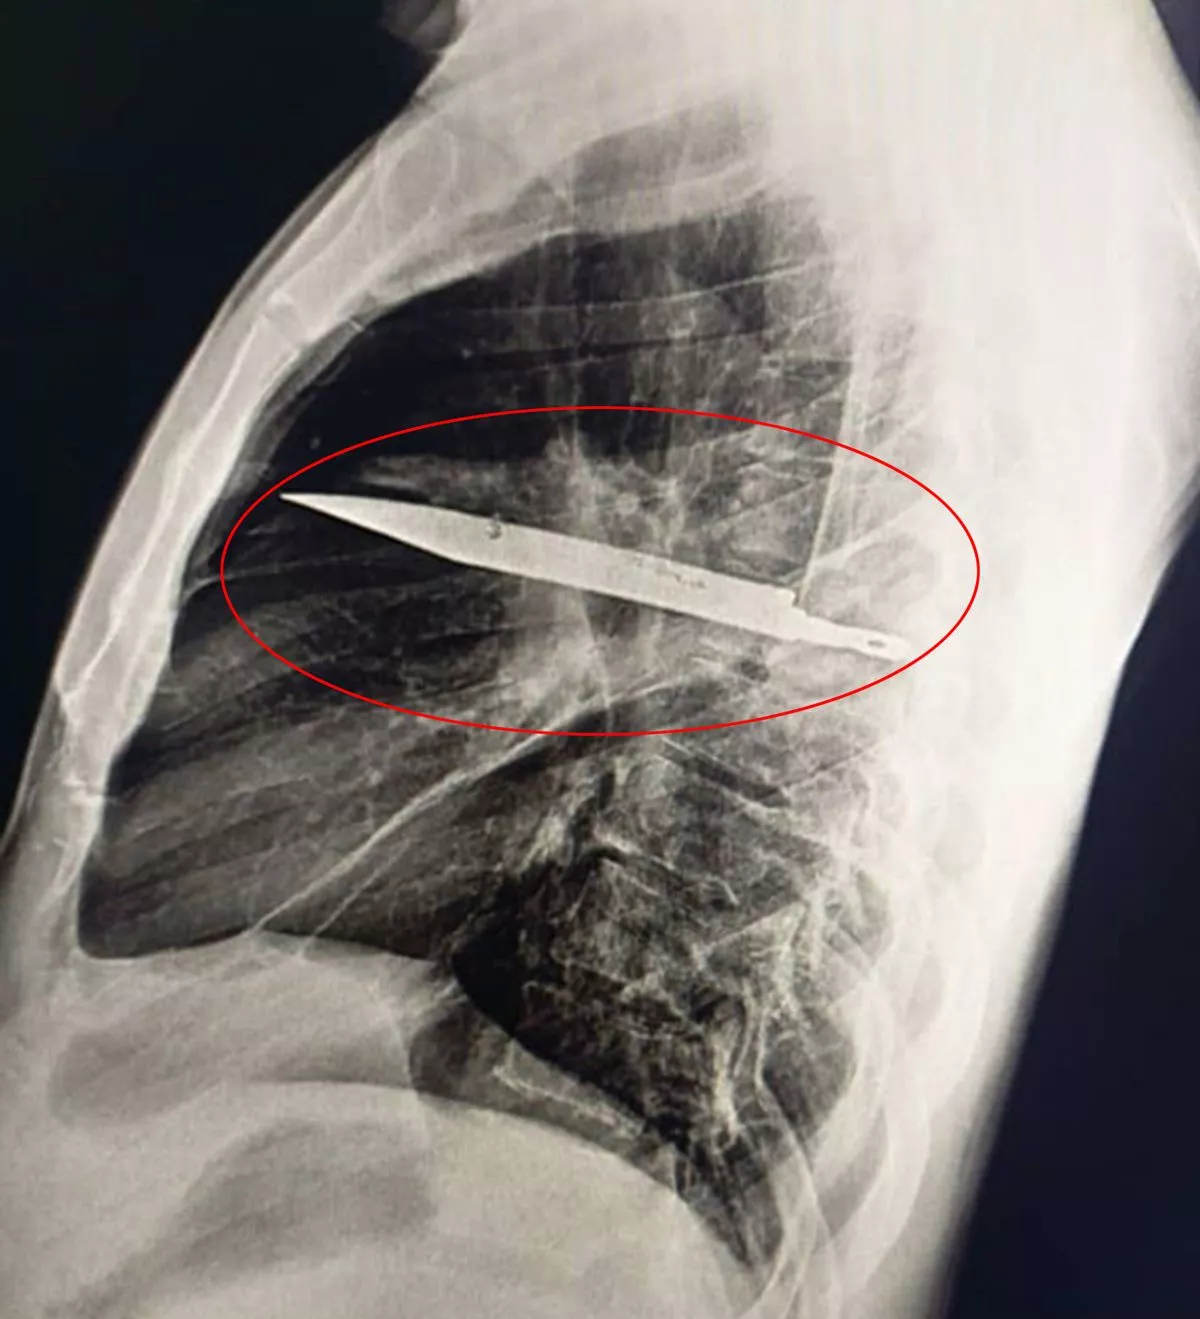

Une radiographie thoracique a été réalisée après sa plainte et elle a révélé la cause de son mal actuel : une grande lame de couteau logée au milieu du thorax. Les médecins ont constaté que le couteau avait pénétré l’omoplate droite et avait réussi à éviter les organes vitaux.Le couteau a été soigneusement extrait pendant l’opération, le pus – dû aux tissus nécrosés – étant drainé simultanément. L’homme, qui ignorait depuis huit ans qu’un couteau était logé en lui, est resté 24 heures aux soins intensifs avant d’être transféré en service général, où il est resté dix jours sous surveillance médicale. Le cas, rapporté par le Journal of Surgical Case Reports en juillet 2025, indiquait que le patient, soigné à l’hôpital national de Muhimbili en Tanzanie, s’était bien rétabli et que les consultations de suivi s’étaient déroulées sans incident.